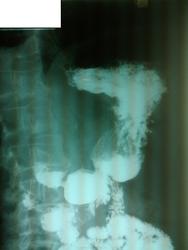

Пациент, 60 лет. На ФГДС: В антральном отделе отмечается некоторая ригидность на малой кривизне, рядом с привратником.

Не вижу изменений в антральном отделе, но обращает внимание некоторая ригидность задне-медиальной стенки субкардиально.

Обратила внимание на уплощение контура на малой кривизне препилорического отдела. Но только на одном снимке, на остальных - без особенностей. Вряд ли стоит придавать этому значение. Вы видели моторику - Вам судить